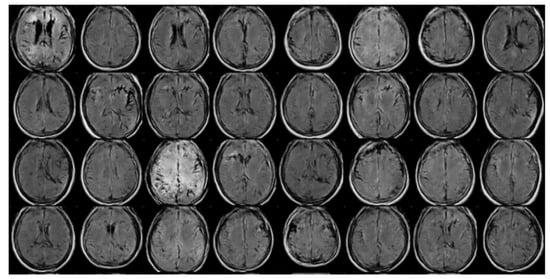

3.1. Dataset

3.1.1. Analysis of Volumes and Slices Dataset

GAN Data Augmentation